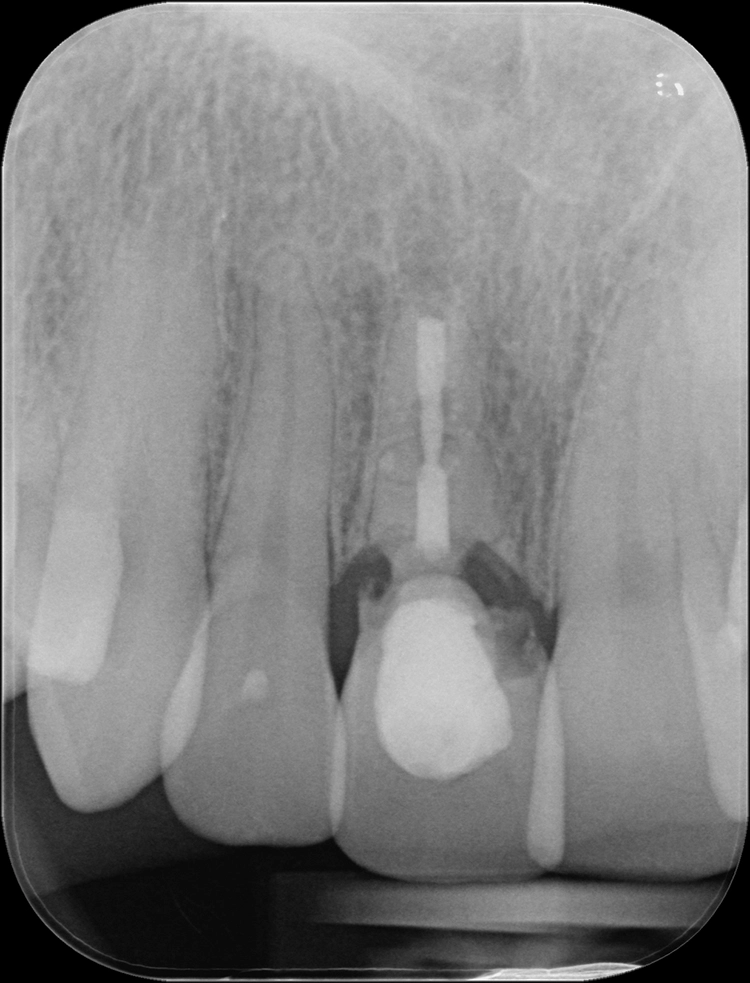

Anschließend wurde der durch die externe Resorption stark angegriffene Wurzelrest schonend entfernt. Bei der Sofortimplantation kommt es auf den Erhalt der lokalen knöchernen Bedeckung an.

Die Alveole wird von Granulationsgewebe gesäubert und direkt postoperativ durch ein Kleinröntgen auf Wurzelreste kontrolliert. Die Aufbereitung des Implantatbettes und die Implantatinsertion erfolgt im apikalen Bereich tendenziell eher palatinal. Im Bereich der Implantatschulter wurde ein Abstand von 2,5 mm zur vestibulären Lamelle eingehalten.

Dr. Blume